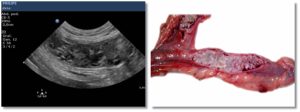

Esta es una sección realizada en colaboración de los compañeros veterinarios con los que trabaja DXIA, en la cual, compararemos imágenes reales, obtenidas durante la resolución quirúrgica, con imágenes ecográficas.

Una forma que puede ser interesante de colaboración y que nos ayuda a poder darle color a las imágenes obtenidas durante un estudio ecográfico seria comparar las imágenes reales que se obtienen durante las cirugías o intervenciones con las imágenes diagnósticas obtenidas durante el estudio ecográfico del paciente. Os quiero animar a todos a que mandéis dichas imágenes y a que este apartado crezca día a día.